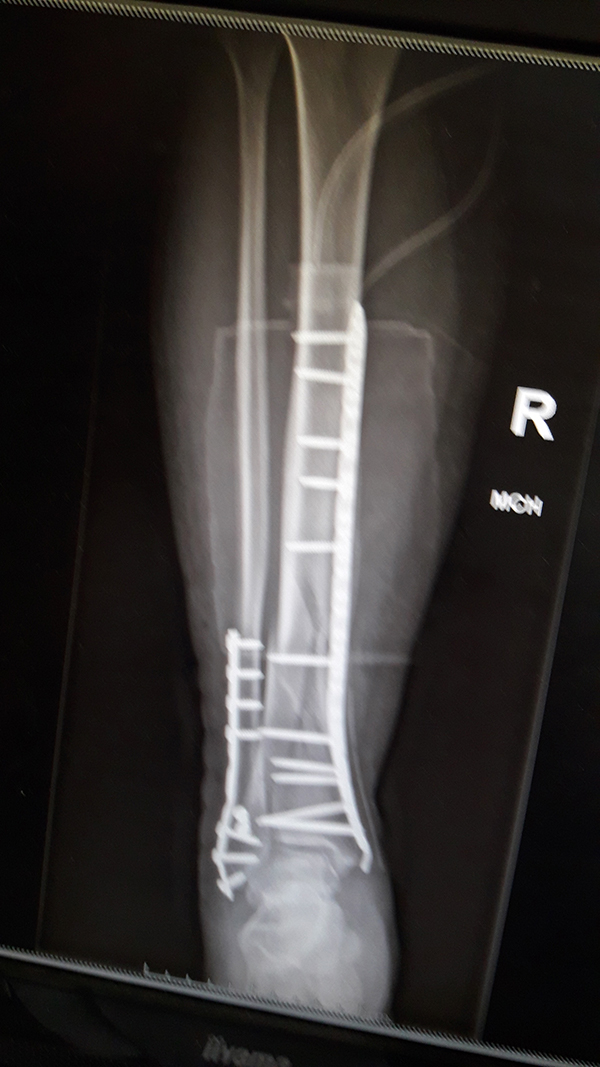

Miednica i kończyna dolna